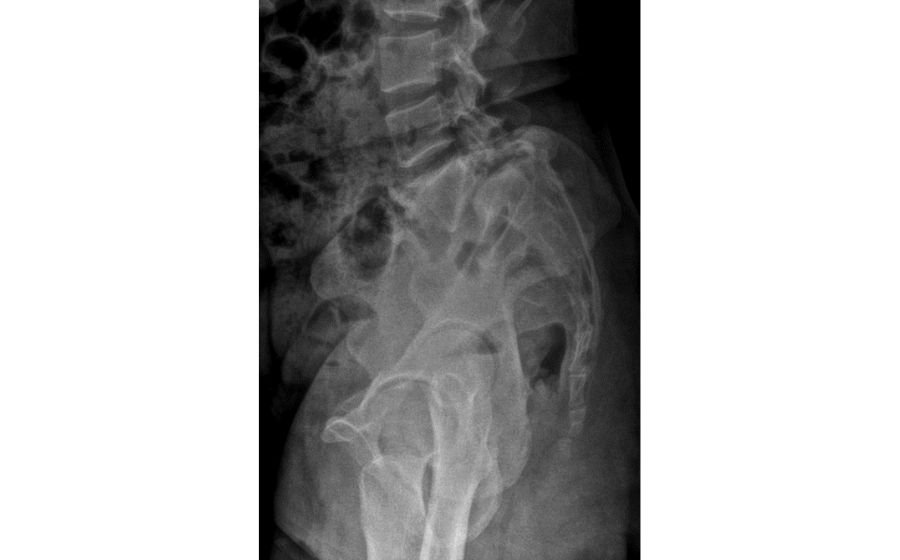

Spondylolisthesis

Spondylolisthesis occurs when one vertebra slips forward over the one below it, often due to aging, arthritis, stress fractures, or congenital weakness. This slippage can narrow the spinal canal and press on nerves, causing back pain, leg pain, tingling, or difficulty standing and walking. Diagnosis is made using X-rays and MRI to assess the degree of slip and nerve compression. Treatment includes physiotherapy, core strengthening, medications, and targeted injections. In cases with instability or persistent symptoms, minimally invasive or fusion surgery helps restore alignment, relieve nerve pressure, and improve long-term stability and mobility.